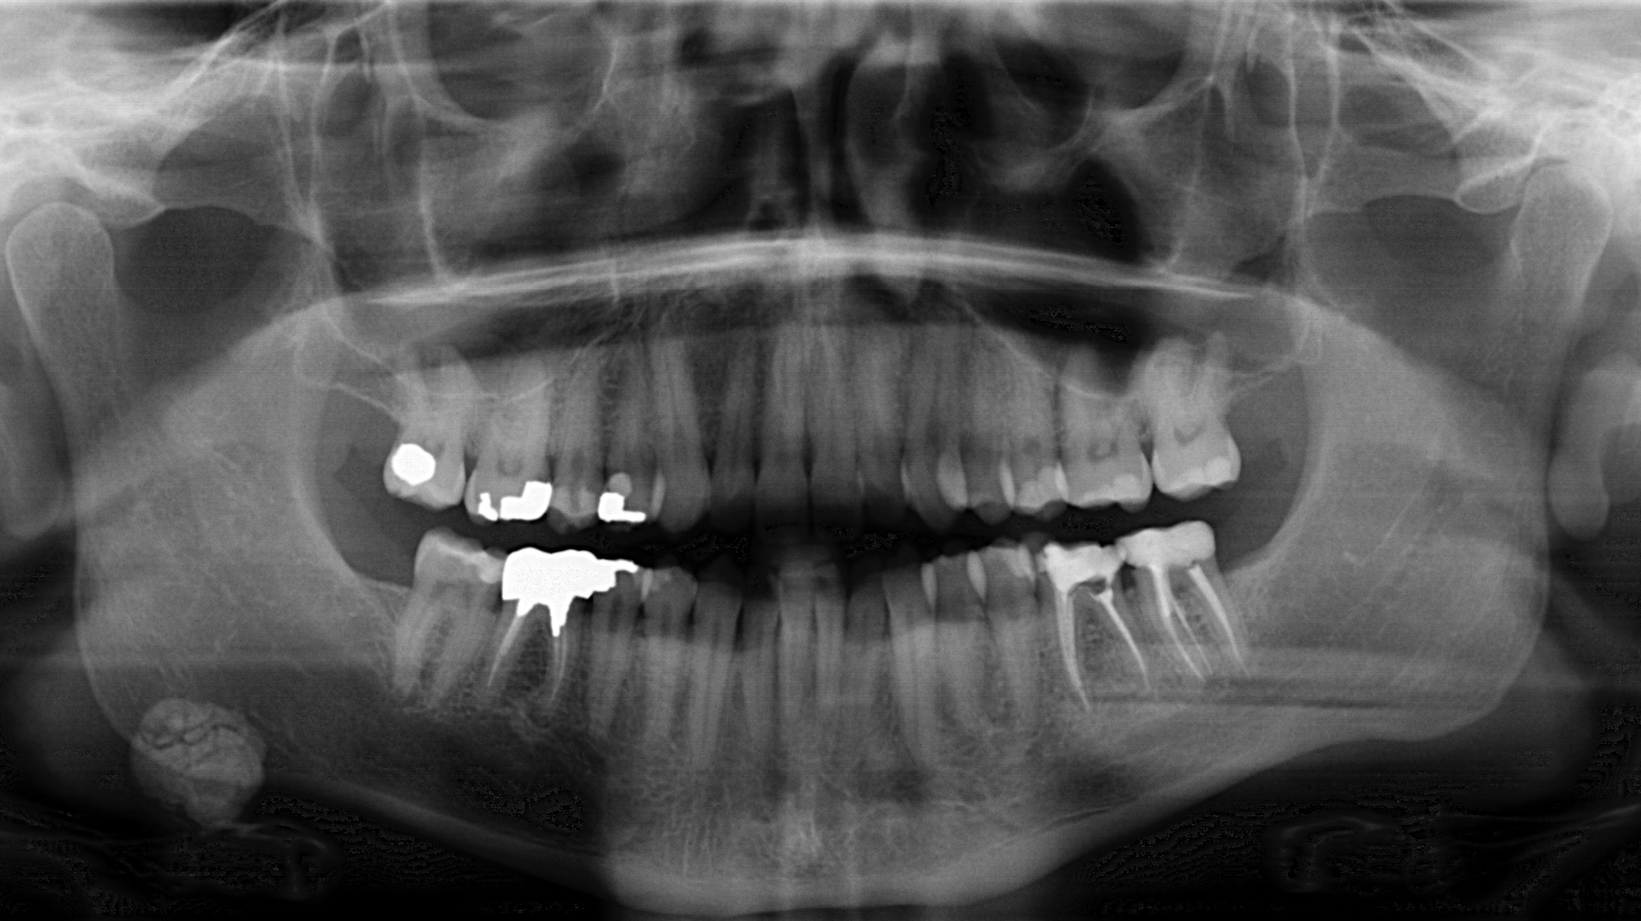

A healthy, 36-year-old male presented for a comprehensive exam. A panoramic radiograph revealed a well-defined, radiopaque lesion approximately 2x2 cm in size in the right submandibular region. The patient was unaware of its existence. The lesion was slightly palpable upon extraoral manipulation, but not necessarily tender.

Sialolith of the right submandibular gland

Sialoliths are calcareous (radiopaque) deposits in the ducts of the major or minor salivary glands or within the glands themselves.1 Nearly 80% of all sialoliths affect major salivary glands, the most common being the submandibular gland.1,2 Predilection for the submandibular gland (~73%) and duct may result from gravity and the fact that the oral terminus is superior to the gland.1 Prolonged blockage can lead to degeneration and eventual shutdown of the gland; salivary retention with ductal dilation results in pain and swelling.2 Glands that are no longer functional become subject to retrograde bacterial infections.1 Any swelling is notably present at mealtimes when there is stimulation for salivary production.

This particular patient was seen by an oral surgeon and a CT scan was obtained. It was recommended that the lesion be removed; however, since the lesion was asymptomatic at the time, the patient was quite reluctant. The patient is seen on a regular basis with subsequent radiograph evaluation to monitor for changes. The recommendation for removal still stands.